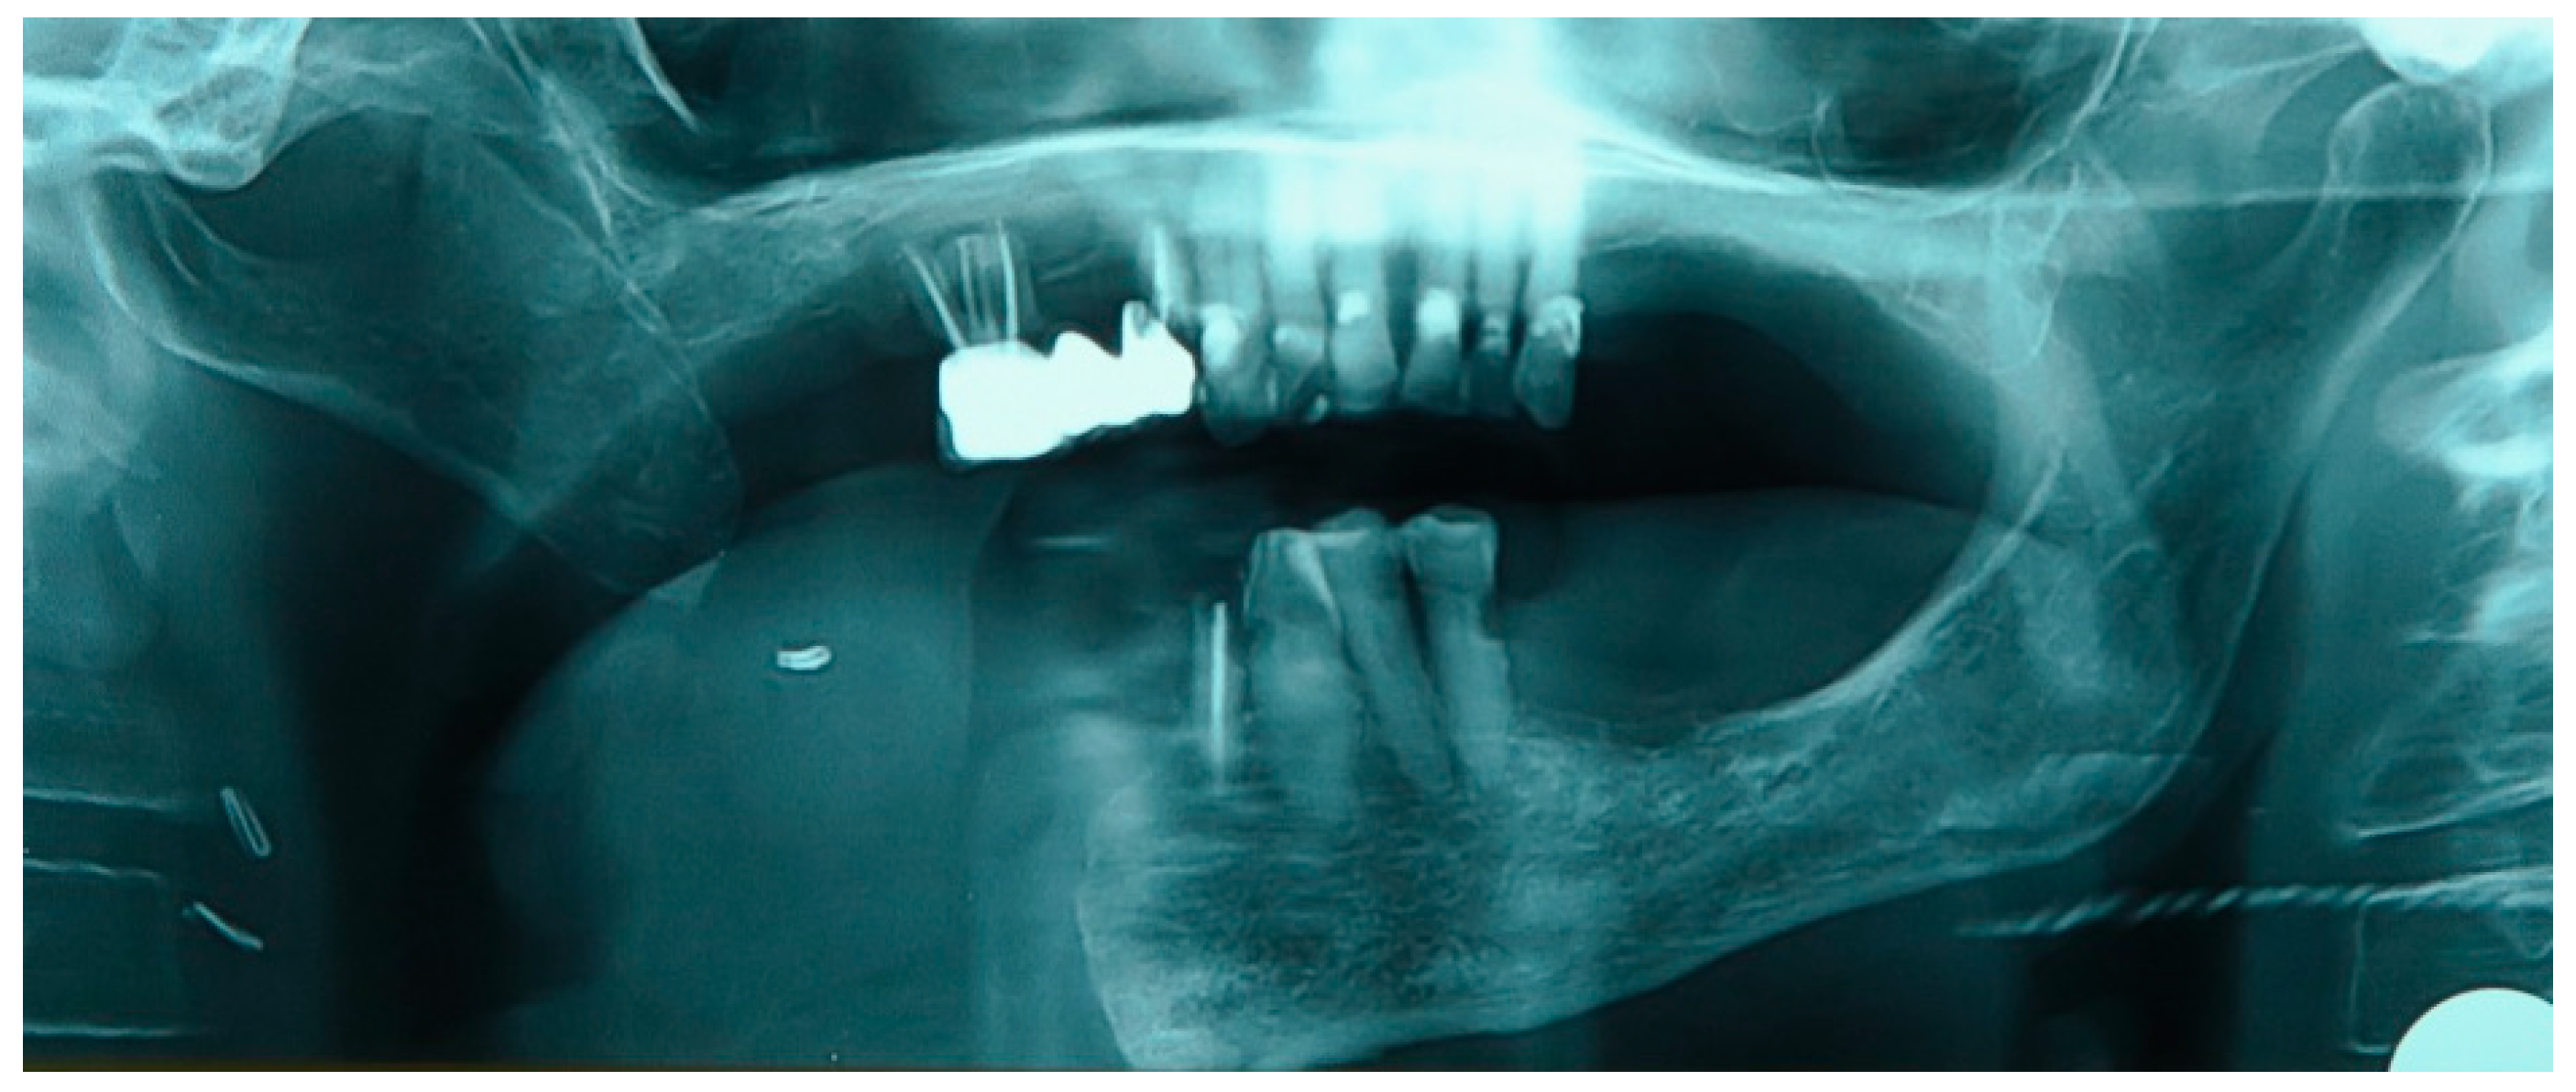

Figure 6. Patient with hemimandibulectomy L2, L3 in orthopanoramic X-ray.

The patient of case 2 presented an L2-3 resection, with preservation of both the condyle and the coronoid process (Figure 5 and Figure 6). Although posteriorly edentulous, the patient had maintained six lower elements (31, 32, 33, 34 (which hosts a prosthetic crown), 41, and 42). The trajectory between open and closed positions is roughly maintained, and the surviving mandible does not tend to swing laterally toward the surgical side during opening (Figure 7).

He required no intermediate removable prosthesis. Although the mandibular resection resulted in a rather extensive bony defect, the placement of three implants in the III quadrant allowed for an intermediate rehabilitation with three prosthetic crowns (Figure 8 and Figure 9). The pictures regarding the result are not yet available, and the rehabilitation project is intended to develop as follows: the prosthetic crowns serve as an occlusal plane guide, helping the patient to find a more centric mandible position.

However, due to the rotational effect of these pivotal points, and the fact that the surviving lower teeth are too lingual to help stabilize the occlusal plane, we plan to extract the remaining lower teeth and potentially utilize GBR techniques to allow the customized placement of two additional implants in the symphysis area, which will in turn support prosthetic crowns, allowing further occlusal points.